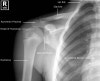

1. Shoulder AP view